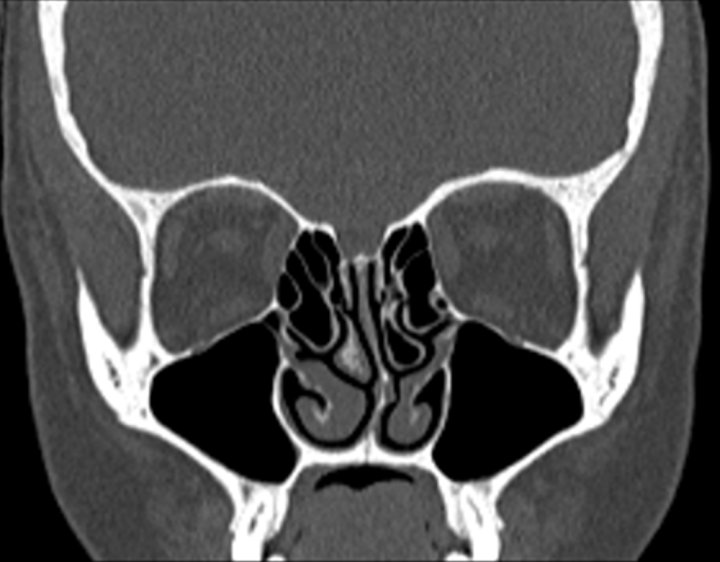

Click any image for labels.